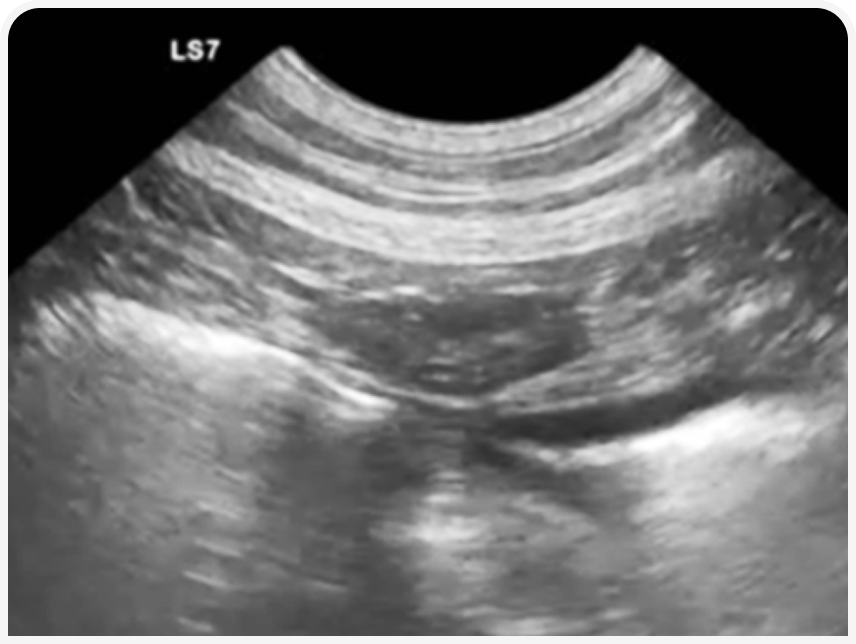

УЗИ в течку будет максимально информативно для определения ОРС. В этот период в корковом слое яичников начинается рост фолликулов, которые у собак около периода овуляции могут достигать размера 1-1,2 см.

При наличии фолликулогенеза яичник приобретает характерную «уникальную» УЗ-картину, что наряду с признаками течки и картиной вагинальной цитологии позволяет подтвердить диагноз ОРС с максимальной достоверностью.

Культя матки и краниальной части влагалища у собак и кошек в течку под действием эстрогенов значительно утолщается за счет отека, стенки становятся гипоэхогенными, картина отличается от периода полового покоя.

УЗИ у кошек с подозрением на ОРС часто затруднительно по причине меньшего размера и необходимости использовать высокочастотные трансдукторы.

Но, как и у сук, в течку яичники будут иметь характерную картину овального образования с множеством кистозных структур размером до 3-4 мм, а культя матки будет утолщаться. Алгоритм проведения исследования аналогичен алгоритму у сук.